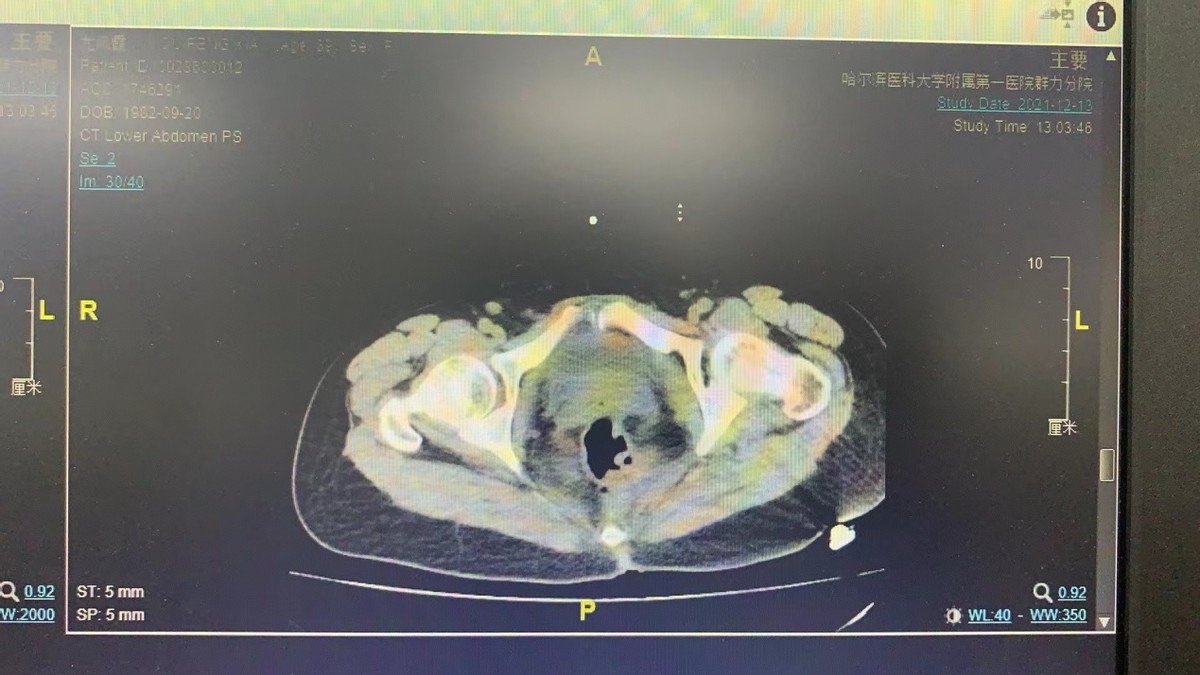

图1术前盆腔CT影像学检查

伊铁忠教授为患者进行详细查体、完善全面检查后,建议手术治疗。为充分评估病情,降低术中并发症,术前请泌尿外科会诊,完善膀胱镜检查,考虑膀胱占位病灶。术前完善盆腹腔CT检查,提示盆腹腔多部位病灶,累及膀胱、盆腔器官,前腹壁、脐周。在完善术前检查后,经多学科会诊,在国家二级教授郑建华专家指导下,决定给予开腹手术治疗。